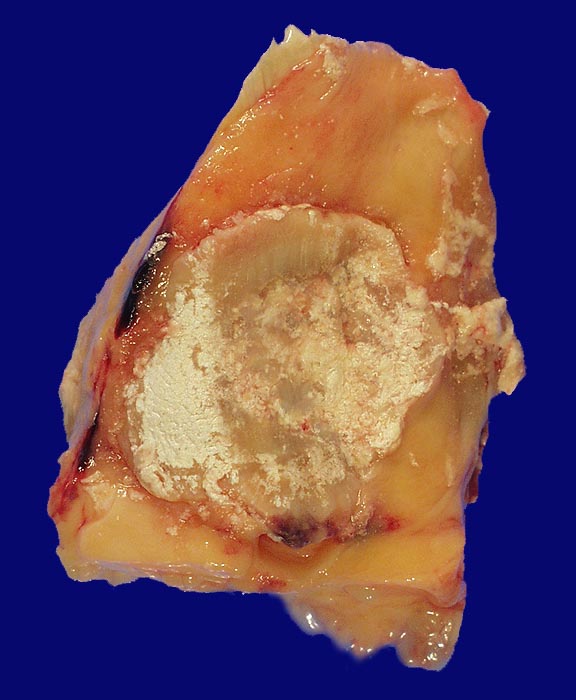

Bei einer Gicht sind kristallin ausgefällte Natriumuratkristalle in den neutrophilen Granulozyten des Gelenkergusses und kalkweisse Auflagerungen am Gelenkknorpel nachweisbar. Kristallablagerungen in Form von Gichttophi mit einer granulomatösen Fremdkörperreaktion finden sich ausserhalb von Gelenken auch in Sehnenscheiden (Achillessehne), Weichteilen (Ohrläppchen, Ellenbogen, Knie), in der Achillessehne oder im Nierenparenchym. Die Löslichkeit von Harnsäure nimmt mit der Umgebungstemperatur ab, sodass die Kristallablagerungen vorwiegend peripher vorkommen. Am häufigsten betroffen ist das Grosszehengrundgelenk (Podagra), gefolgt von Sprunggelenk, Ellenbogengelenk, Kniegelenk und anderen Gelenken an Fuss und Hand.

• Kollagenes Bindegewebe mit Tophus bestehend aus wolkiger eosinophiler Matrix mit herdförmig erkennbaren nadelförmigen Strukturen (Uratkristalle).